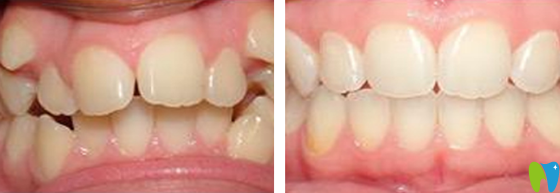

3、牙齒矯正

年齡:14歲

牙齒癥狀:地包天

治療方法:時代天使隱形矯正

患者點評:諾德口腔真心舒服,環(huán)境溫馨豪華,關鍵是正畸醫(yī)生非常專業(yè),兒子有輕微地包天,用了8個月左右,完成的牙齒正畸,現(xiàn)在擁有了一口整齊的牙齒,非常感謝諾德的張醫(yī)生。

深圳諾德齒科時代天使隱形矯正案例